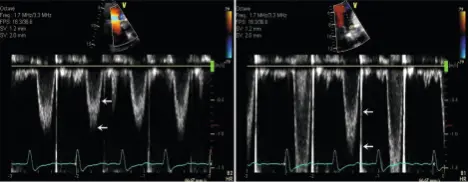

• Caption from Figure 4-6 of Oh Textbook: Examples of LVOT PWD velocity recording in a patient with atrial fibrillation. The sample volume needs to be placed about 5 mm from the aortic annulus to avoid flow acceleration. The spectral broadening (interval between two arrows with turbulent flow) should be less than 40 cm/s (left). The sample volume is too close to the aortic valve or too large in the example shown (right). Of note, there is some variation of LVOT velocity in this example because of atrial fibrillation.

• Normal values for LVOT peak velocity: 0.9 to 1.1 m/s

• Normal values for TVI: 20 to 24 cm.